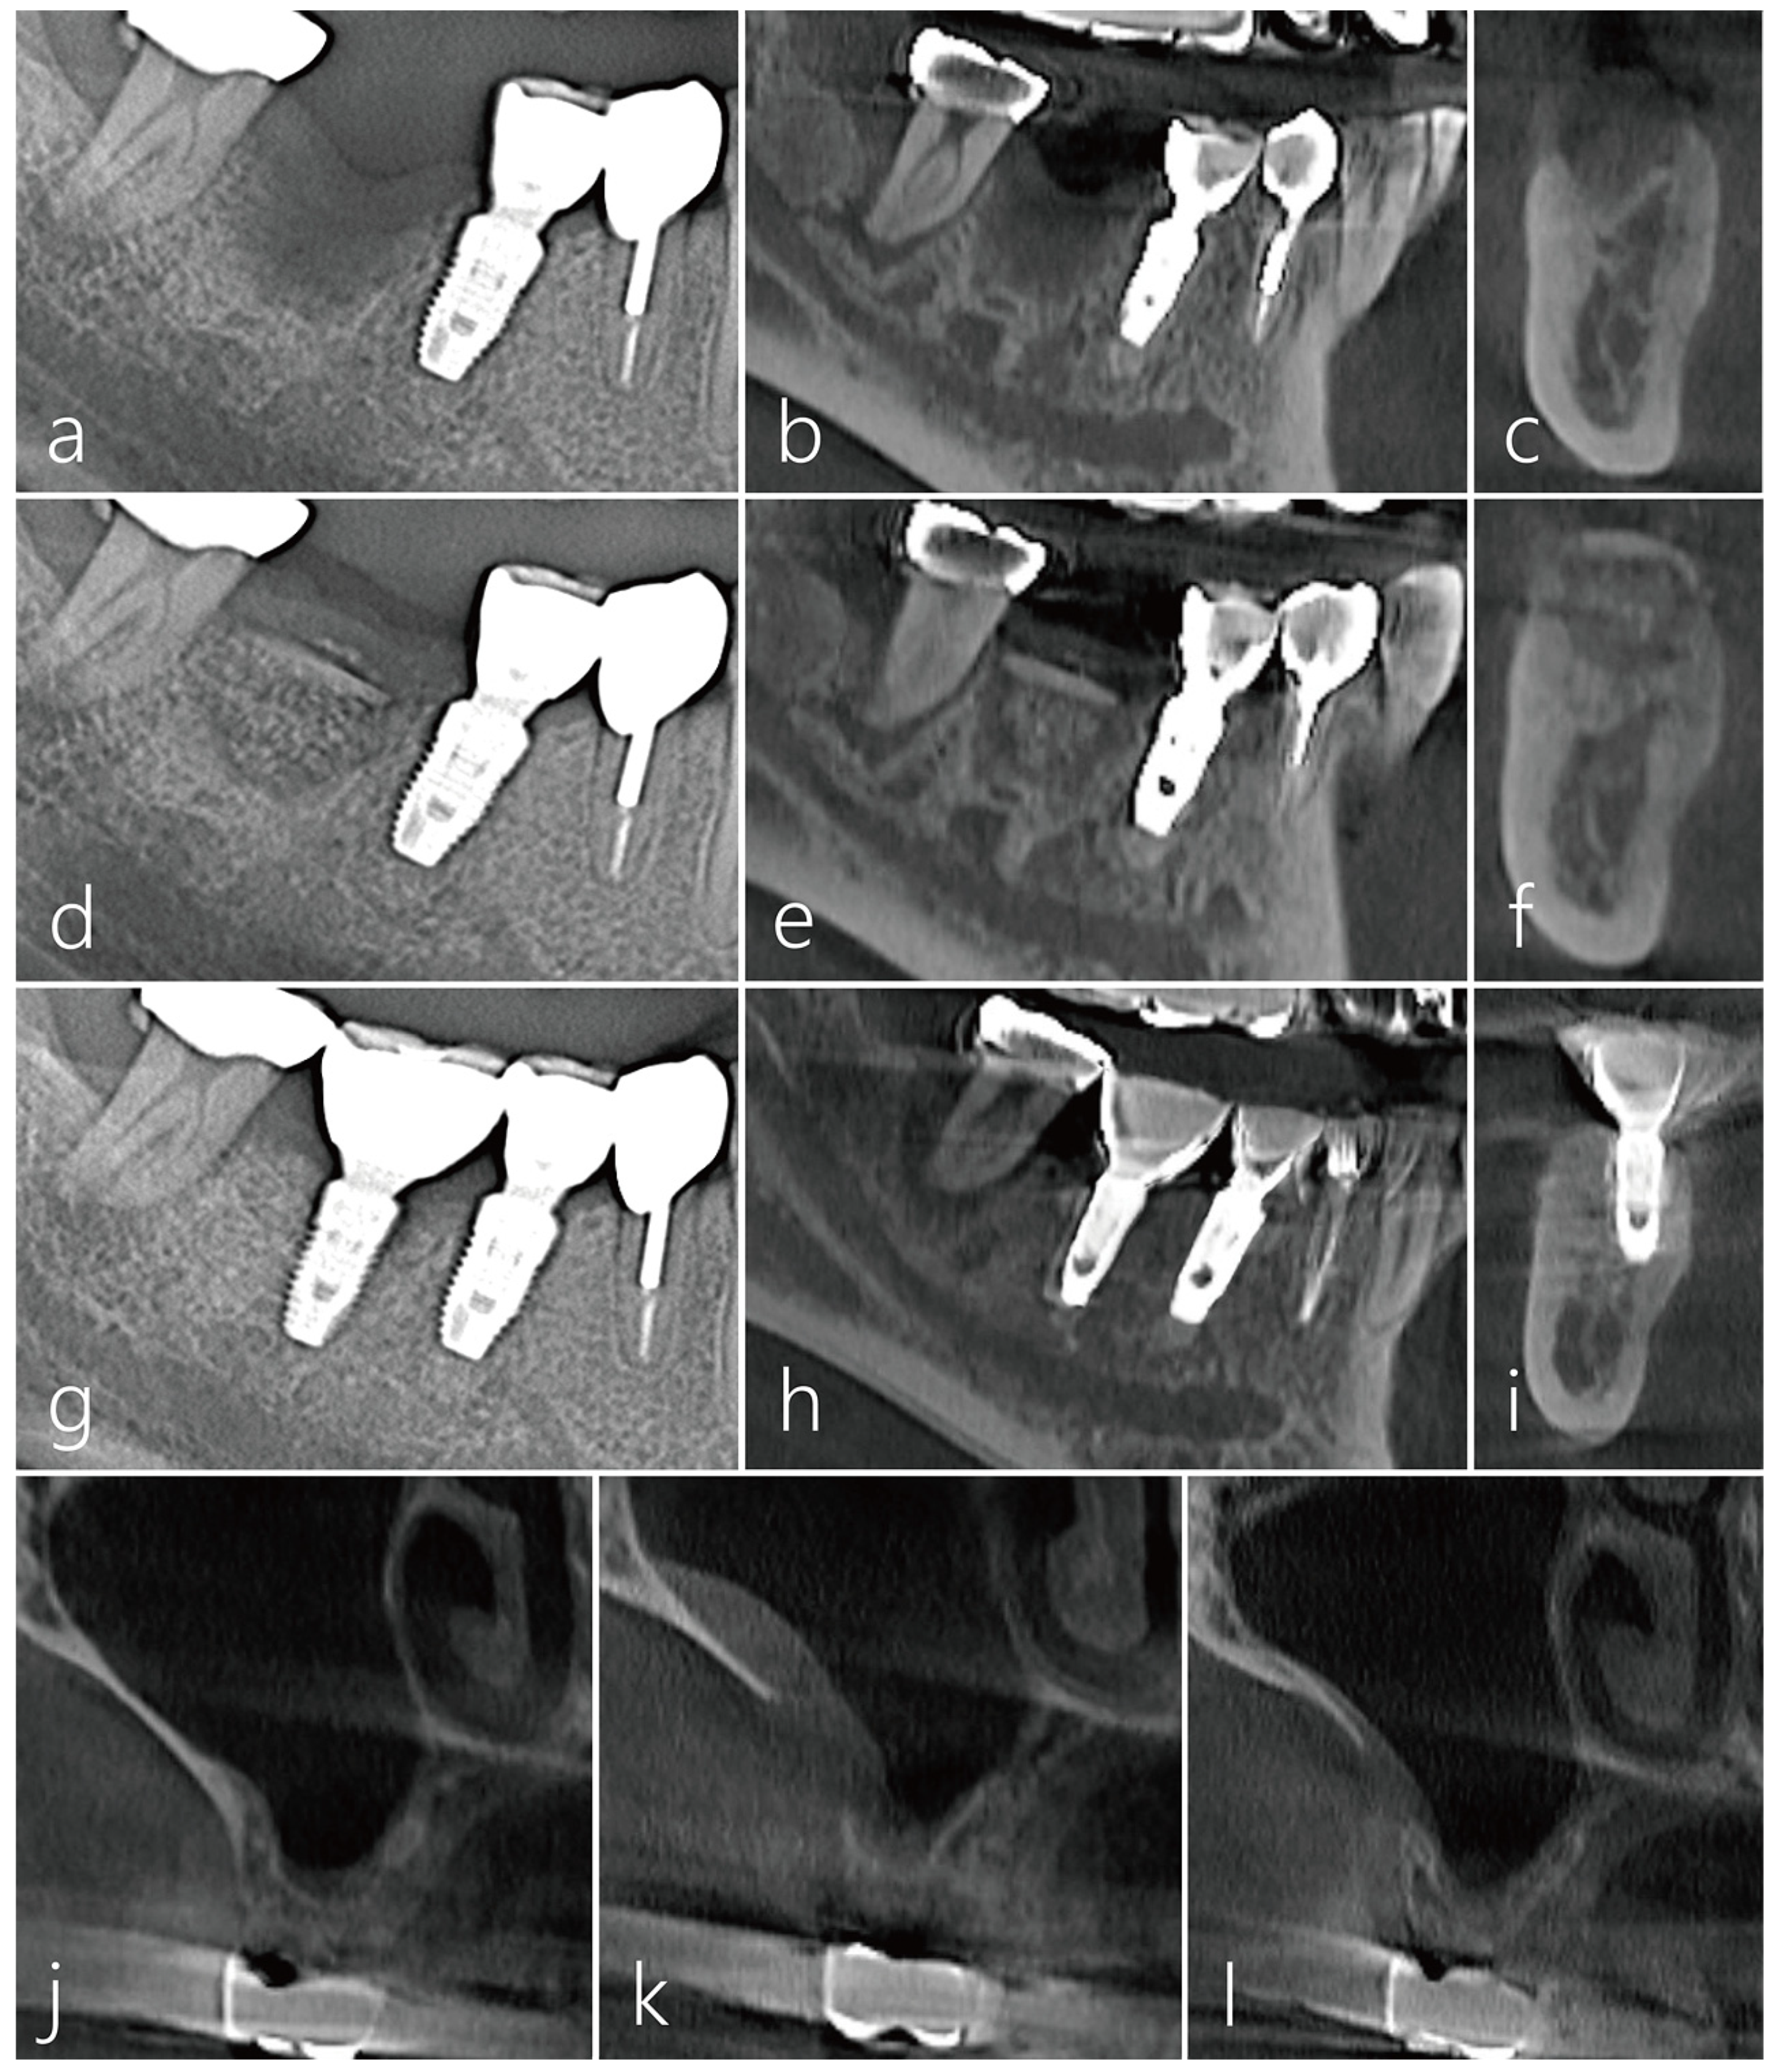

2.1. Case 1

2.2. Case 2